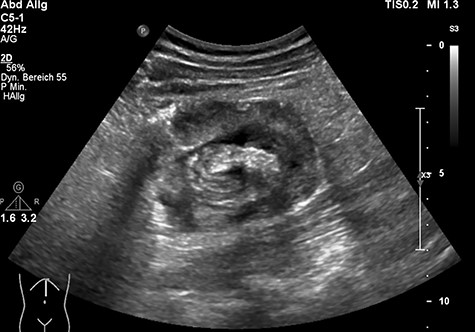

The clinical examination showed a slightly deteriorated condition and a painful distended abdomen with tenderness in all quadrants. There was no rebound pain or palpable masses. Blood tests showed a normal white cell count with a very slight elevation in C-reactive protein (7 mg/l). In the emergency department, the first diagnostic approach with ultrasonography revealed a circular concentric layer, with a maximum diameter of 4–5 cm, highly suspicious of invagination in the left upper quadrant (Fig. 1). The second step was to perform a CT scan with consequent confirmation of the diagnosis. The exam revealed a long ileocolonic intussusception of the ascending colon into the transverse colon, with possible involvement of the terminal ileum; a suspicious strangulation of a superior mesenteric artery branch was postulated (Figs 2 and 3).

Ultrasonography with a circular concentric layer highly suspicious of invagination.